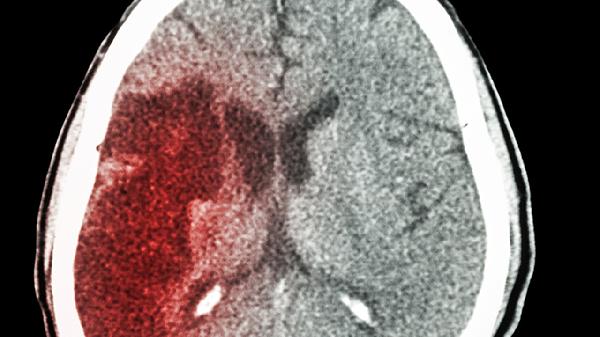

• 宝宝摔后脑出血有哪些表现

宝宝摔倒后如果出现脑出血,常见的表现包括意识不清、频繁呕吐、瞳孔大小不一致、抽搐以及嗜睡等。脑出血可能由颅骨骨折或脑血管...